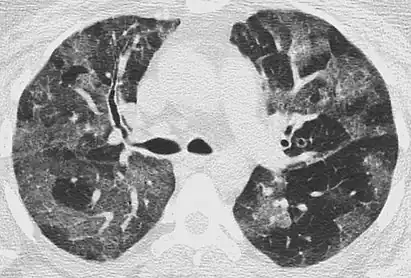

CT image showing mosaic attenuation pattern in patient with hypersensitivity pneumonitis. Note the alternating, patchy areas of increased and decreased attenuation, particularly in the left lung (screen right).

Mosaic

A mosaic pattern of GGO refers to multiple irregular areas of both increased attenuation and decreased attenuation on CT. It is often the result of occlusion of small pulmonary arteries or obstruction of small airways leading to air trapping.[6] Sarcoidosis is an additional cause of a mosaic GGOs due to the formation of granulomas in interstitial areas. This may coexist with granulomatosis with polyangiitis, leading to diffuse areas of increased attenuation with ground-glass appearance.[6]